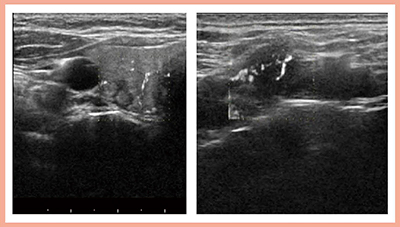

症例2はびまん性硬化型乳頭癌で,微細石灰化を多数伴うため,通常の超音波では石灰化表面で超音波が反射して描出不能となることが多いが,4G CMUTでは石灰化の状態だけでなく,内部血流までが明瞭に観察可能である(図2)。また,甲状腺乳頭癌の術前評価においては,術後気管切開の必要性を判断するために気管浸潤の有無を評価する必要があるが,症例3では4G CMUTにて気管と腫瘍との境界が明瞭に描出され,術前に浸潤なしと判断できた(図3)。

図2 症例2:びまん性硬化型乳頭癌の石灰化(a),血流(b),エラストグラフィ(c)の描出